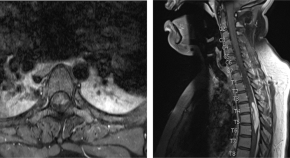

Spinal cord ischaemia is a rare complication following the gluteal injection of Benzathine benzylpenicillin. The hypothesis is embolization of the Penicillin products retrogradely through the Superior gluteal artery and cause occlusion of the vasculature that supply the spinal cord. This article includes literature review of the hypothesis behind the Spinal cord ischaemia and highlights the previous cases reported.